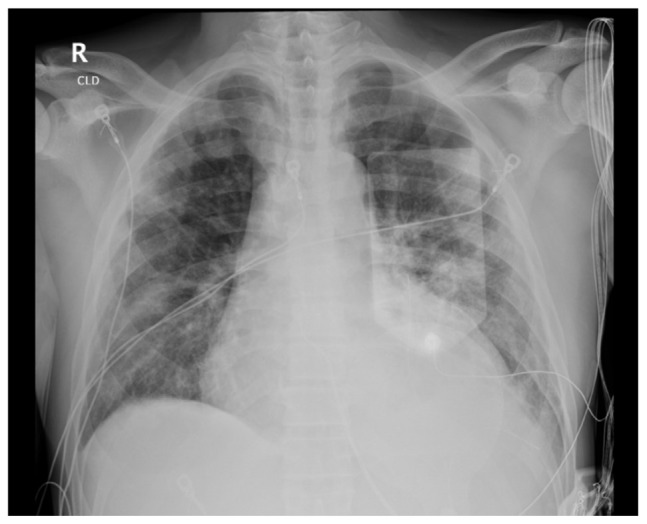

伊鲁替尼,一种布鲁顿酪氨酸激酶抑制剂,已经改变了各种血液系统恶性肿瘤的管理。然而,它与心血管毒性,特别是心房颤动(AF)、高血压和心力衰竭(HF)的关联引起了临床关注。心包积液虽然罕见,但也是一种值得注意的新并发症。我们报告一个62岁男性淋巴浆细胞性淋巴瘤的病例,最初用苯达莫司汀和利妥昔单抗治疗,由于明显的中性粒细胞减少而停止治疗。开始伊鲁替尼治疗,3个月时部分缓解。伊鲁替尼治疗约10个月后,患者出现新发呼吸困难、心悸和头晕。心电图显示房颤伴心室快速反应,经胸超声心动图(TTE)显示左心室射血分数降低40%,心包积液中度。使用依鲁替尼之前的基线评估显示心脏功能正常。考虑到心力衰竭伴射血分数降低和心包积液的发展,停用依鲁替尼。患者开始接受指南指导的心力衰竭药物治疗。6个月后,患者表现出明显的心脏恢复,射血分数恢复正常,心包积液消失。虽然心房颤动和心力衰竭被认为是依鲁替尼的不良反应,但心包积液很少被报道。鉴于伊鲁替尼的使用日益增加,临床医生应对心血管并发症保持警惕。早期识别和管理对于降低与这些不良反应相关的发病率和死亡率至关重要。该病例强调了对接受伊鲁替尼治疗的患者进行全面心血管监测的重要性,并有助于越来越多的关于其心脏毒性的文献。

Ibrutinib, a Bruton's tyrosine kinase inhibitor, has transformed the management of various hematological malignancies. However, its association with cardiovascular toxicities, particularly atrial fibrillation (AF), hypertension, and heart failure (HF), has raised clinical concerns. Pericardial effusion, though rare, is an emerging complication warranting attention. We present the case of a 62-year-old male with lymphoplasmacytic lymphoma, initially treated with Bendamustine and Rituximab, which was discontinued due to significant neutropenia. Ibrutinib therapy was initiated, leading to a partial response at three months. Approximately ten months into ibrutinib treatment, the patient developed new-onset dyspnea, palpitations, and dizziness. ECG revealed AF with rapid ventricular response, and transthoracic echocardiogram (TTE) showed a reduced left ventricular ejection fraction of 40 % and a moderate pericardial effusion. Baseline assessments prior to ibrutinib had indicated normal cardiac function. Given the development of heart failure with reduced ejection fraction and pericardial effusion, ibrutinib was discontinued. The patient was initiated on guideline-directed medical therapy for heart failure. Over six months, the patient exhibited significant cardiac recovery, with normalization of ejection fraction and resolution of the pericardial effusion. While atrial fibrillation and heart failure are recognized as adverse effects of ibrutinib, pericardial effusion is less commonly reported. Given the increasing use of ibrutinib, clinicians should maintain vigilance for cardiovascular complications. Early recognition and management are crucial to mitigate morbidity and mortality associated with these adverse effects. This case highlights the importance of comprehensive cardiovascular monitoring in patients receiving ibrutinib and contributes to the growing body of literature on its cardiotoxic profile.